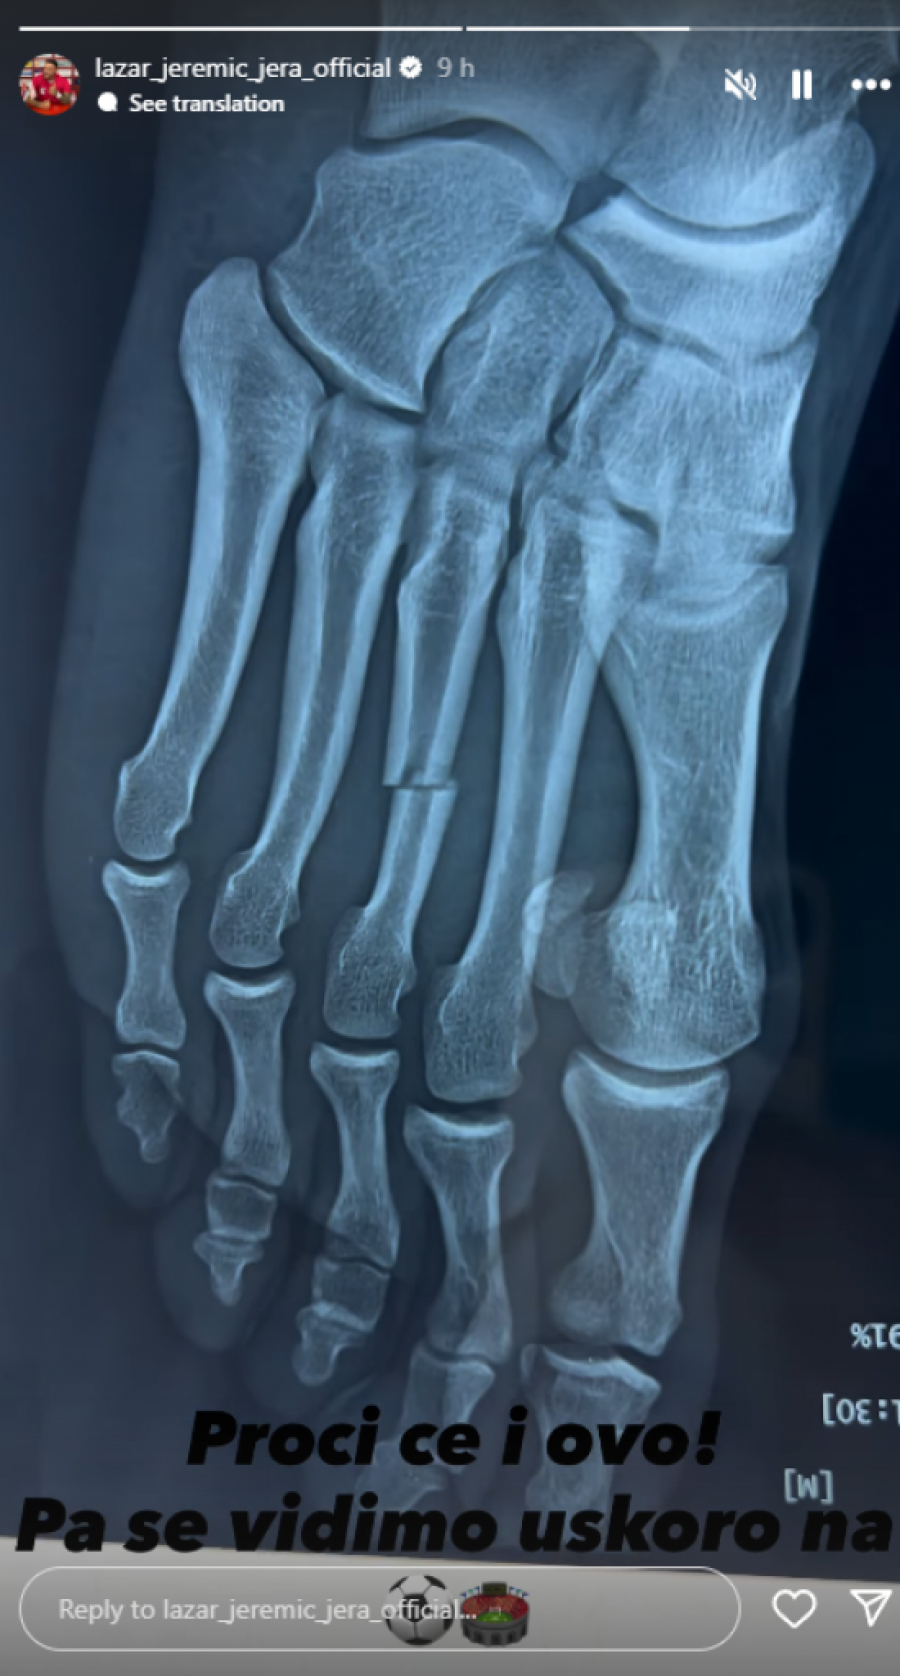

Bivši rijaliti učesnik Lazar Jeremić nedavno je izazvao pažnju svojih pratilaca na Instagramu objavivši snimak iz bolnice. Na snimku se vidi kako leži na bolničkom krevetu sa nogom u gipsu, što je odmah izazvalo brigu među njegovim fanovima. Jeremić je u opisu snimka objasnio da mu je kost pukla na dva dela, što će značiti da će njegov oporavak trajati duže od očekivanog. Ova situacija nije nova za njega, jer je već ranije imao operaciju zbog koje je dugo odsustvovao iz svoje fudbalske karijere.

Zanimljivo je da Lazar nije stranac povredama. Njegova prethodna operacija, koja je rezultirala dugim oporavkom, ukazuje na to da se povrede u sportu često dešavaju, ali i na to koliko su ozbiljne. Fudbal je fizički zahtevna igra, a povrede su nažalost deo svakodnevnice mnogih sportista. Lazarova trenutna situacija naglašava koliko je važno brinuti se o svom zdravlju i rehabilitaciji, kako bi se povratak na teren uspešno ostvario.